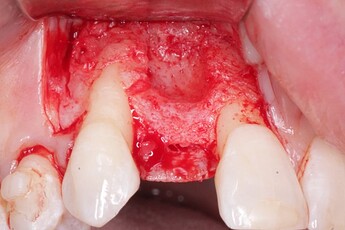

Pic 3

osseoseal-3

An implant was placed in site #7 with an existing buccal bone defect (Pictures 1 & 2). Prior to placing the bone graft over the implant, the membrane is measured and trimmed and tucked under the palatal flap trying to avoid wetting the entire membrane (Picture 3). The particulate bone graft (DALI Classic Cortical Cancellous Mix) is placed over the implant surface to restore the defect (Picture 4). The membrane is folded over the crest and onto and slightly beyond the particulate bone graft while slowly dropping saline onto the membrane (Picture 5). This enables the membrane to contour and drape over the graft and “seal” the graft off from the surrounding soft tissue (Picture 6 and 7). Sutures are then used to achieve primary closure over the GBR site (Picture 8).